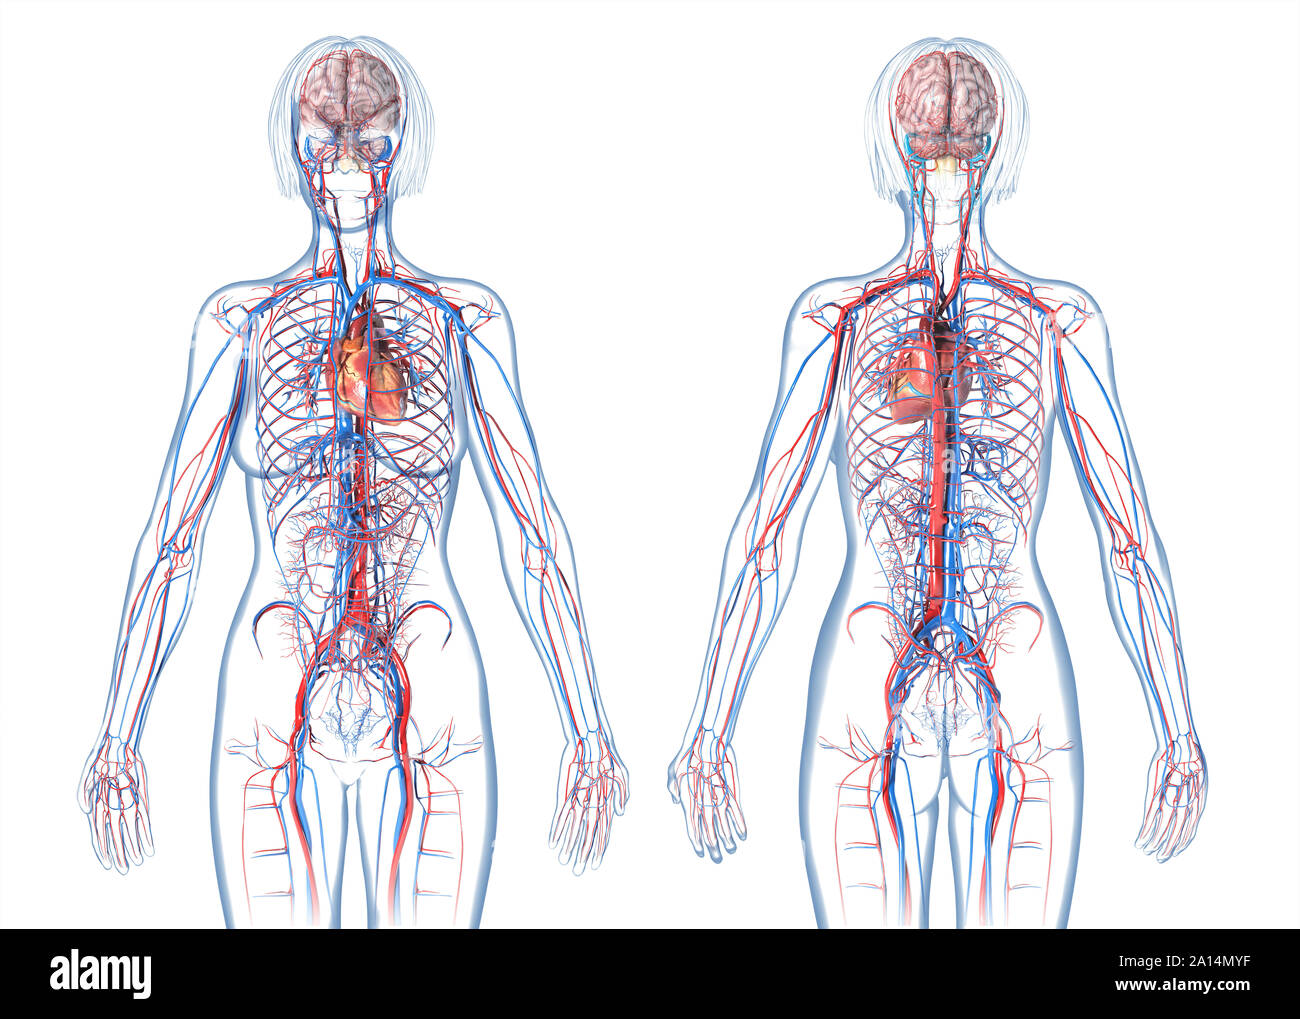

Анатомия человека: кровеносная система и её связь со скелетом